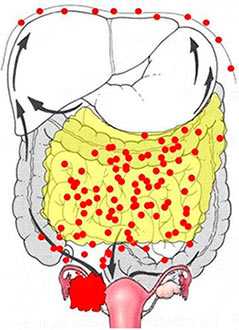

Опухолевые клетки могут распространяться не только через кровеносные и лимфатические сосуды, но и «расползаясь» по брюшине.

Самая большая проблема в диагностике и лечении метастатического рака кишечника и других органов в том, что метастазов обычно много, многие из них имеют микроскопические размеры и не видны на снимках, их нельзя обнаружить и удалить во время хирургического вмешательства.

Канцероматоз брюшины при раке толстой кишки

Если раковые клетки распространяются в брюшину, прогноз сильно ухудшается. Возникает асцит — в брюшной полости скапливается жидкость. Для борьбы с этим состоянием прибегают к лапароцентезу — в брюшной стенке делают прокол и выводят жидкость. Для постоянного оттока жидкости устанавливают перитонеальный катетер. Проводят внутриполостную химиотерапию, по показаниям выполняют хирургические вмешательства, направленные на обеспечение оттока жидкости из брюшной полости.